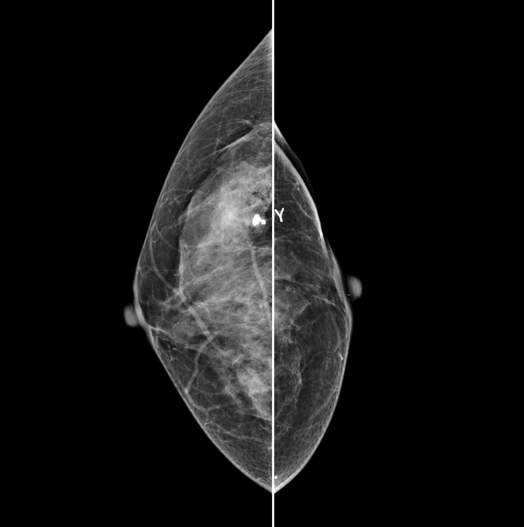

The X-ray tube moves on the breast and takes high-definition, high-resolution images with high contrast from various angles.

The images are reconstructed in 3D to provide accurate information about the location and condition of the lesion.

HESTIA supports "Synthetic 2D" that generates 2D images only by tomography shooting without additional 2D shooting.